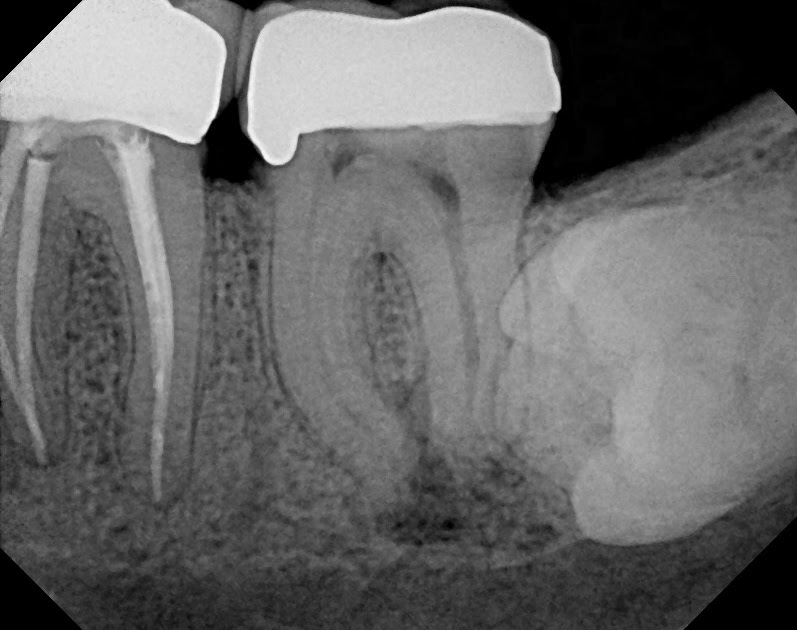

Root canal retreatment of a molar with periapical pathology Norfolk Endo Apical Diagnosis Apical fenestrations associated with endodontic infections are relatively uncommon and can easily be overlooked or misdiagnosed. Endodontic diagnosis clinical newsletter defines aae and abe terminology to help understand the progressive nature of pulpal and periapical. In endodontics, an accurate diagnosis is imperative to identify the offending tooth. It’s essential that you always have a pulpal and a periapical diagnosis for. Endo Apical Diagnosis.